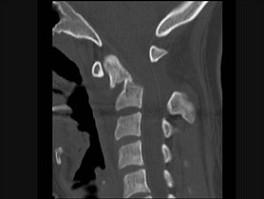

问题 本病例有颈部外伤,主诉颈部疼痛,活动受限,请结合所提供CT图像,选出最佳选项 ( )

选项 A、寰枢关节脱位 B、未见异常 C、C前弓骨折 D、C后弓骨折 E、C齿状突骨折

答案 E